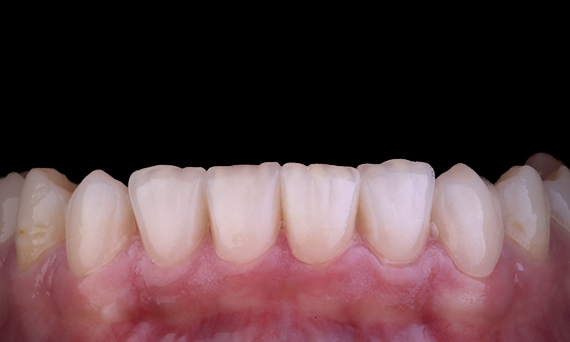

Het is vrij gebruikelijk om scheuren en breuken waar te nemen die verband houden met amalgaamrestauraties, vooral omdat ze groter worden omdat het “ongebonden” restauraties zijn. Veel van deze tanden zijn structureel aangetast en een zelfklevende, biomimetische aanpak is de ideale methode om deze tanden te herstellen. In het kader van een uitgebreider behandelplan is gepland dat dit kwadrant twee indirecte keramische onlays krijgt. De eerste en tweede molaren werden bij één bezoek gerestaureerd met CEREC Tessera, een geavanceerd lithiumdisilicaat.